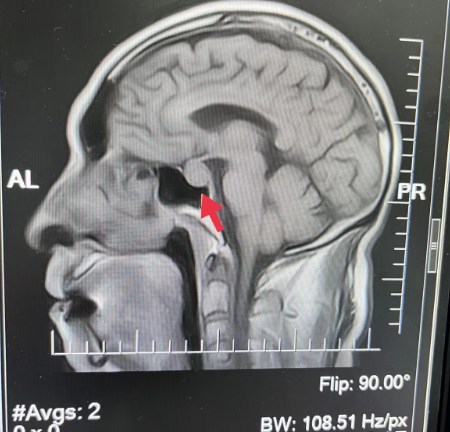

10、**男士,69岁

2023年9月8日在银川仁泰体检部体检,脑核磁检查提示:矢状位显示垂体窝内T2、T1WI示16.8*14.4mm等信号影,考虑脑垂体窝占位性病变,2023年9月12日通知客户到三甲医院进一步检查,明确病变性质,2023年9月20日跟踪回访,客户反馈已确诊为垂体瘤,正在住院做术前准备。